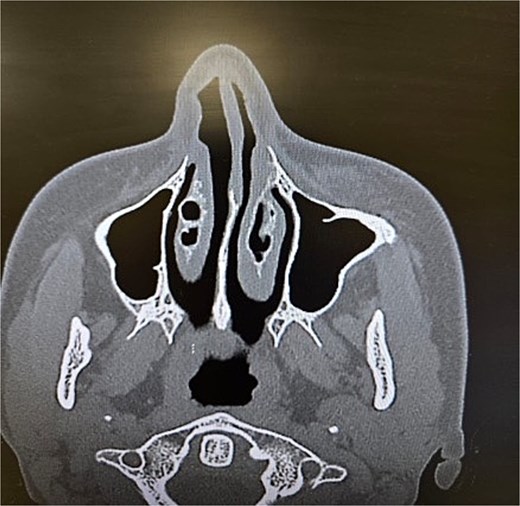

Anterior rhinoscopy and nasal endoscopy demonstrated bilateral hypertrophy of the inferior and middle turbinates, with clear and patent sinus ostia and no evidence of polyps or masses. A coronal CT scan of the paranasal sinuses revealed bilateral ICB and a unilateral CB of the left middle turbinate (Figs 3–5).

Paranasal sinus CT scan in the axial plane demonstrating inferior concha bullosa.